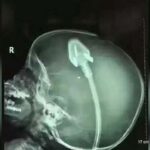

Principais sintomas que podem indicar AVC.

Intensa dor de cabeça que surge de repente;

Redução da força em um dos lados do corpo, braço ou perna;

Perda da sensibilidade em uma região do corpo com mudança de temperatura;

Dificuldade de ficar de pé ou ficar sentado, corpo cai para um dos lados, ao andar arrasta uma das pernas;

Alteração na visão fica embaçada;

Rosto assimétrico, com boca torta ou sobrancelha caída;

Dificuldade para levantar o braço, não consegue segurar objetos;

Fala meio embolada, lenta;

Movimentos com tremores;

Sonolência que pode levar a perda de consciência;

Confusão mental;

Náuseas e vômitos.